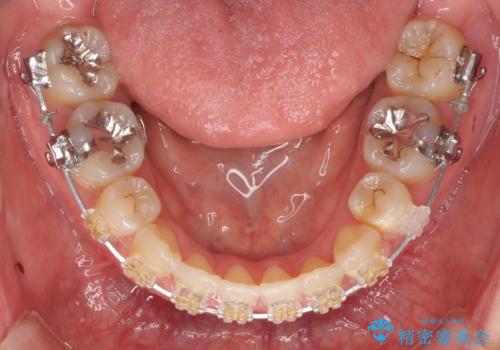

- 矯正装置

- ワイヤー矯正

- 前歯のがたつきを主訴に来院。

前歯のクロスバイト、上の前歯の正中が右にずれていました。

上下左右の小臼歯を抜歯しています。

治療の後半に地方に転居され、2か月に一回の調整となり結果、治療期間がかかりました。

通院はしっかりしていただいたため、無事終了することができました。